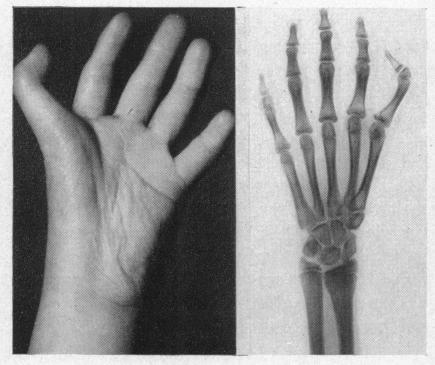

Familial heart disease with skeletal malformations.

Br Heart J. 1960 Apr;22(2):236-42. doi: 10.1136/hrt.22.2.236.